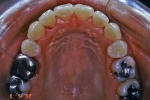

マルチブラケット終了時

|